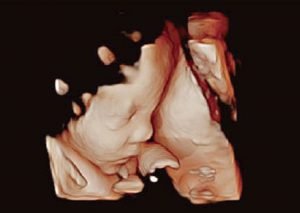

Imágenes 5D